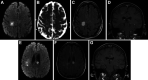

Figure 2.

MRI Brain showing progressive microhemorrhages over course of illness and PET imaging revealing systemic imaging findings. (A) Axial susceptibility-weighted image demonstrating multifocal susceptibility artifact especially involving right parietal cortex at initial presentation. (B) Axial susceptibility-weighted image at corresponding level and (C) more inferior level taken from patient’s fourth hospital admission demonstrating progressive microhemorrhages over the course of illness. (D) Whole-body PET scan during the fourth admission revealing diffuse R humeral FDG avidity and focal avidity in L humeral diaphysis.